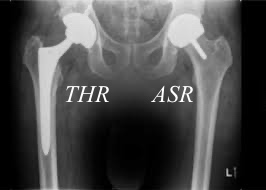

Back home, I was diagnosed with acute osteoarthritis. The orthopedic surgeon said I needed a total hip replacement (THR). He illustrated the procedure with a skeleton doll.

A new alternative was an Articulating Surface Replacement (ASR). Instead of cutting the femur off, it is prepared and capped. No time-to-failure was given, but if the ASR failed, I could refit with a THR and then another THR after that. This extended the worst case to age 80 and was likely to last the rest of my life. Furthermore, the ASR will tolerate running and parachute landings. SOLD!